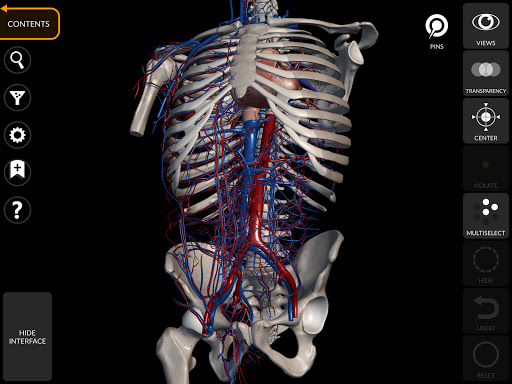

"Anatomy 3D Atlas" дозволяє легко та інтерактивно вивчати анатомію людини.

Завдяки простому та інтуїтивно зрозумілому інтерфейсу можна спостерігати кожну анатомічну структуру під будь-яким кутом.

Анатомічні 3D-моделі особливо деталізовані та мають текстури з роздільною здатністю до 4k.

Поділ за регіонами та попередньо визначені види полегшують спостереження та вивчення окремих частин або груп систем і зв’язків між різними органами.

АНАТОМІЧНІ 3D МОДЕЛІ

• Кістково-м’язова система

• Серцево-судинна система

• Обертайте та збільшуйте кожну модель Тривимірний простір

• Можливість приховування або ізоляції однієї чи кількох вибраних моделей

• Фільтр, щоб приховати або відобразити кожну систему

• Функція прозорості